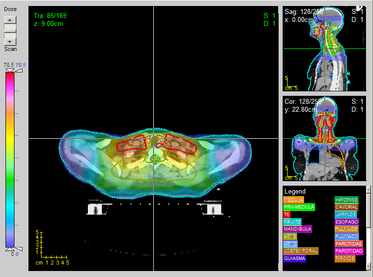

eam

A

ngle

O

ptimisation (

BAO

) in

I

ntensity

M

odulated

R

adiation

T

herapy (

IMRT

)